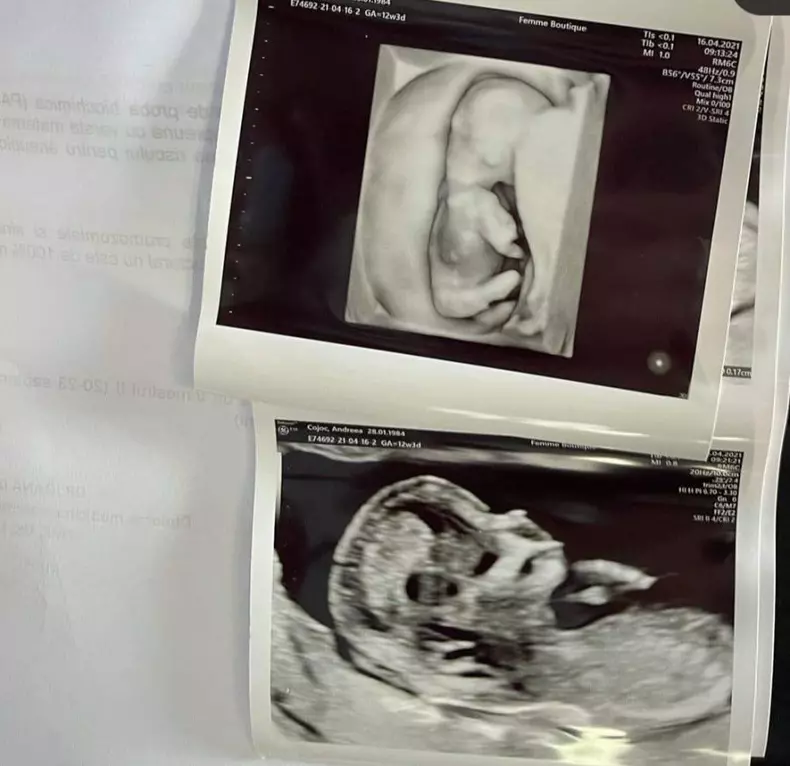

Andreea Popescu, fosta dansatoare a Deliei, va avea fetiță! Ce nume i-a ales: ”Înseamnă Înviere”